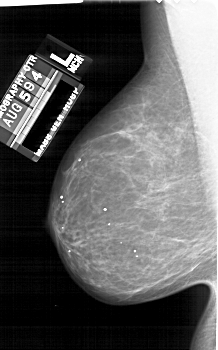

A_1689_1.RIGHT_MLO

RIGHT_MLO LINES 6211 PIXELS_PER_LINE 3481 BITS_PER_PIXEL 12 RESOLUTION 43.5 OVERLAY